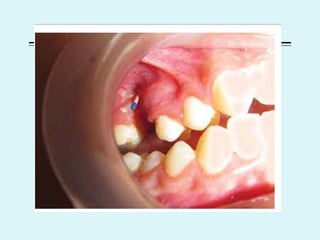

OROANTRAL FISTULA

 Communication between maxillary antrum and oral cavity

 Aetio

 Dental extraction

 Failure of sublabial incision to close

 Carcinoma

 Fractures of maxilla

 Osteitis – syphilis, malignant granuloma

 Clinical features

 Food regurgitation- into nose

 Antral discharge- foul smelling from infected antral mucosa

 Inability to build positive or negative pressure in the mouth ( holding air

within mouth or drinking from straw)

 Diagnosis

 Probe test

 CT PNS

 Treatment

 Recent – if no infection – suturing of margins and antibiotics

 Chronic – palatal or buccal flap, dental obturators, removing fistulous

tract

 CALDWELL LUC surgery is both the cause and treatment of oroantral

fistula